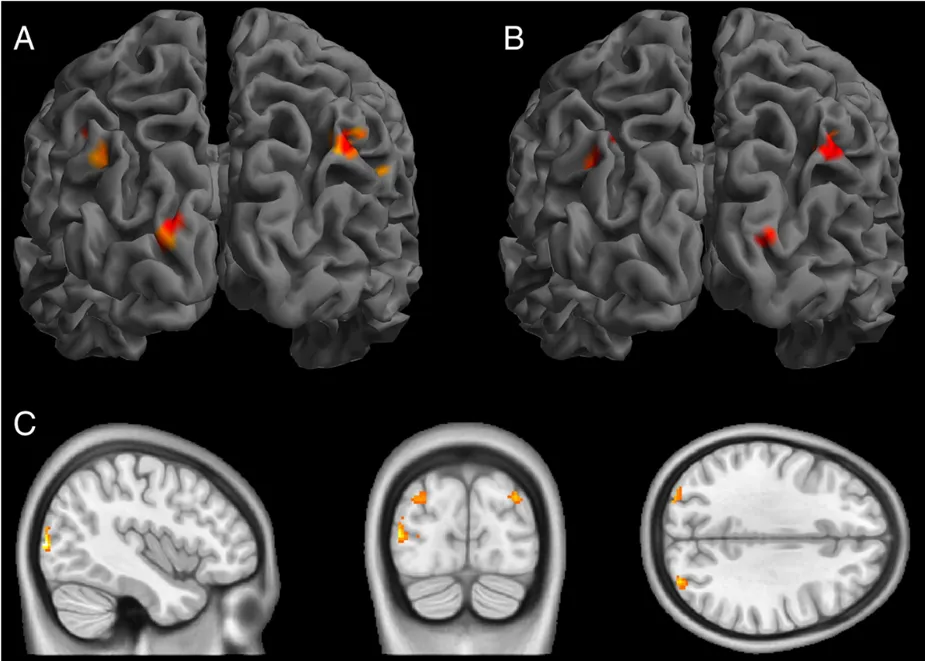

图A(右视野)vs 图B(左视野):表示在进行经颅直流电刺激(tDCS)和视觉刺激时,视野中的BOLD信号增加的区域。(p < 0.001,簇大小 ≥ 40)图C展示了电流刺激与视觉刺激位置之间的统计交互作用。伪刺激没有引起BOLD反应的任何可检测变化。随后,对比阳极tDCS和伪刺激效果的统计分析证实了电流引起的变化局限于枕叶区域。关于刺激的后效应,未观察到显著的电流特异性BOLD变化。

图2 结果经颅直流电刺激(tDCS)与伪刺激的结果